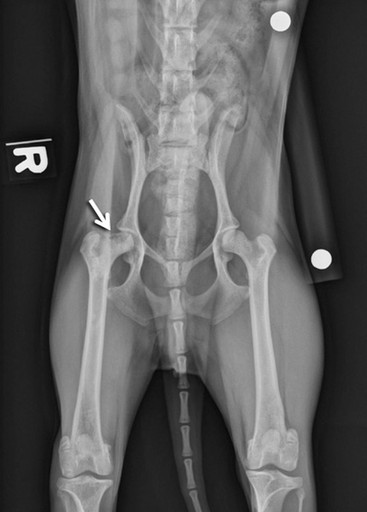

Avascular Necrosis

Avascular necrosis of the femoral head, also known as Legg-Calvé-Perthes disease in humans, is a condition in which the blood supply to the femoral head and neck becomes compromised. Without adequate blood flow, the bone tissue deteriorates (necrosis), leading to collapse and deformity of the femoral head. This process results in chronic pain and progressive loss of hip function.

The condition most commonly affects very young, small breed dogs. Early signs often include a mild but persistent hindlimb lameness that gradually worsens over time. In some cases, the lameness may become suddenly severe if a fracture develops within the femoral head or neck as the bone weakens.

Diagnosis is made with radiographs of the pelvis and hips that show the characteristic bone loss or deformity of the femoral head.

Both hips can be affected so it is important to assess both sides carefully